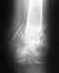

Здравствуйте, прошу посмотреть мои снимки. Что может быть не правильно? Каков исход данной операции? На данный момент прошло 3-мес. Вопрос по тыльному сгибанию стопы стоит остро потому как его практически нет,есть только 90'гр.

Поэтой одной проекции особых проблем не вино. Может, что-то не так на профильном снимке. Движения надо разрабатвать в любом случае.